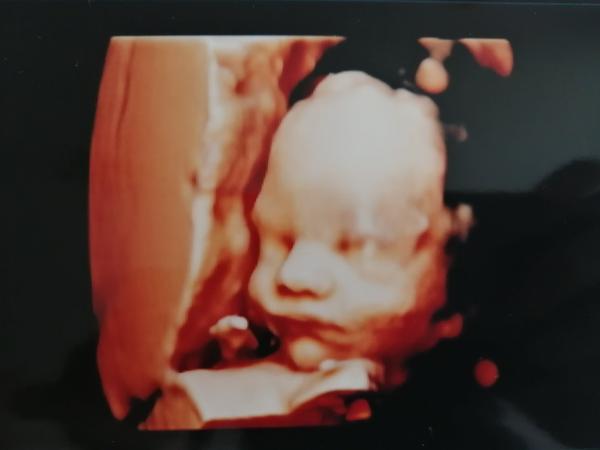

Ve 26-28.tt s obouma synama jsem byla cca v gennetu ☺️A za me parada ..u prvnihu tehu me diky tomu konecne nekdo rekl co čekame 😂

@markytkynka jooo ten druhej syn teda trochu stavkoval ale nakonec se umoudril☺️ A ta cena je vsude cca stejna ☺️